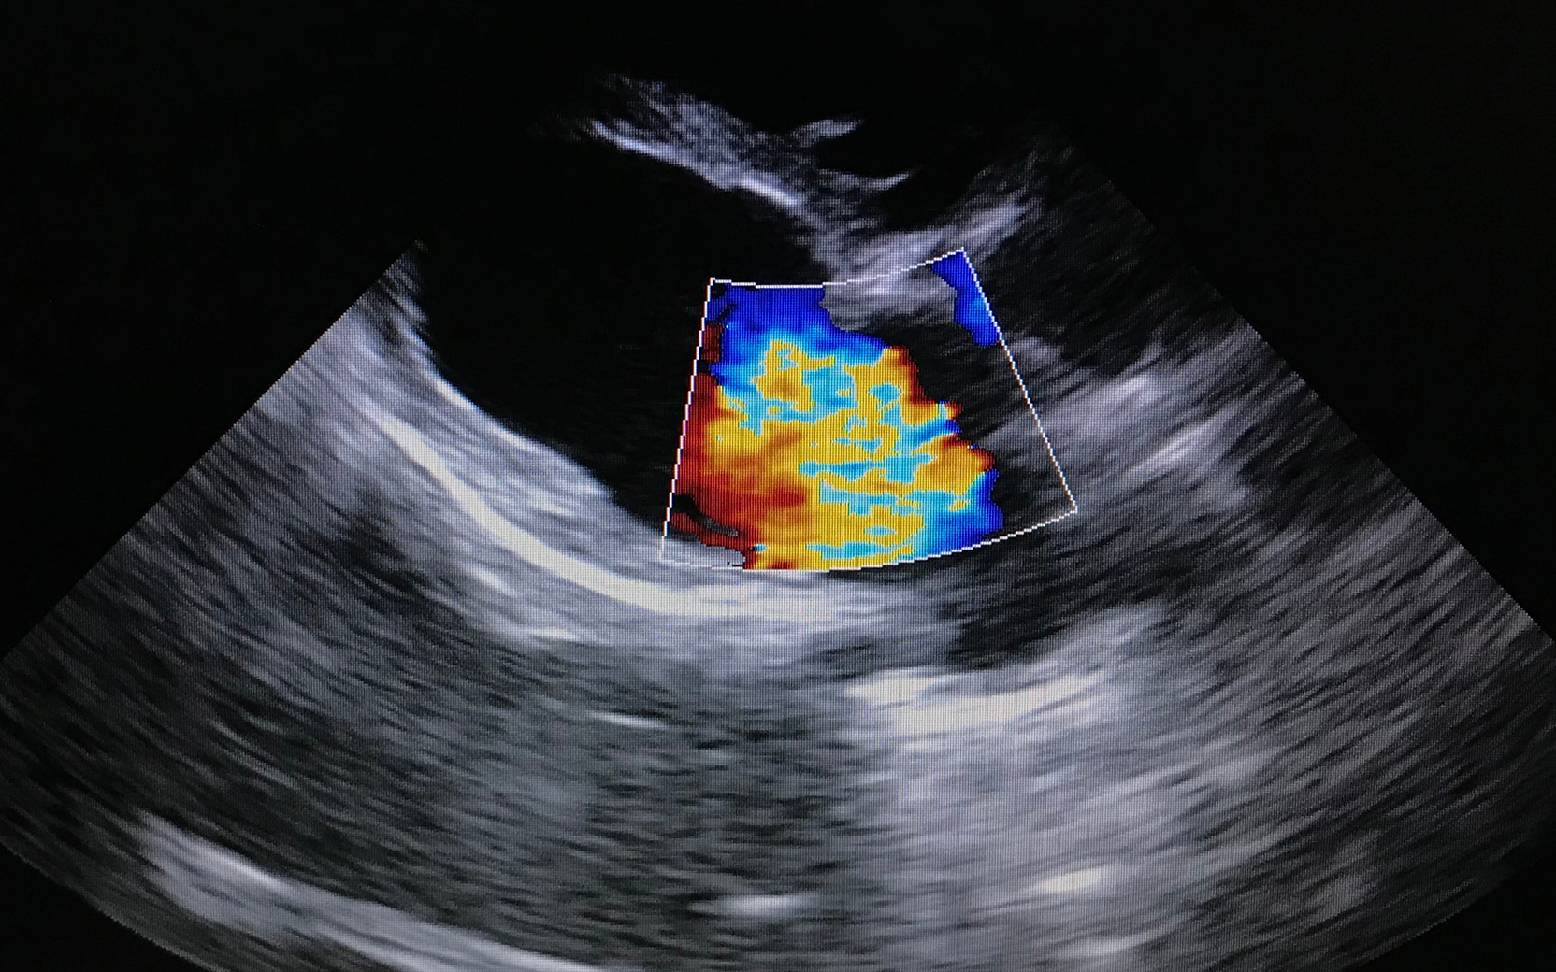

Die Mitralklappe ist eine Segelklappe und liegt zwischen dem linken Vorhof und der linken Herzkammer. Sie verhindert, dass Blut während der Anspannungsphase aus der Herzkammer zurück in den Vorhof strömt. Im Falle einer MMVD kommt es zu einer nicht entzündlichen Veränderung der Gewebestruktur der Klappen. Sie verdicken sich und die Klappenränder können sich einrollen, so dass sich die Klappe nicht mehr vollständig schließen kann und damit undicht wird. Es kommt zu einem zunehmenden Rückstrom von Blut in den linken Vorhof.

Auf die allgemeine Untersuchung folgt die spezielle Untersuchung des Herzens. Dabei wird das Herz zuerst abgehört (=Auskultation) und abgetastet. Meist kann anhand des hörbaren Herzgeräusches bereits eine erste Verdachtsdiagnose gestellt werden. Zur Sicherung der Diagnose ist jedoch die Herzultraschalluntersuchung unerlässlich, in welcher sich der Rückstrom des Blutes genau darstellen und messen lässt. Zusätzlich können Röntgen-, EKG- (=Elektrokardiogramm) und Blutdruckuntersuchungen die Diagnose bestätigen und weiter spezifizieren.